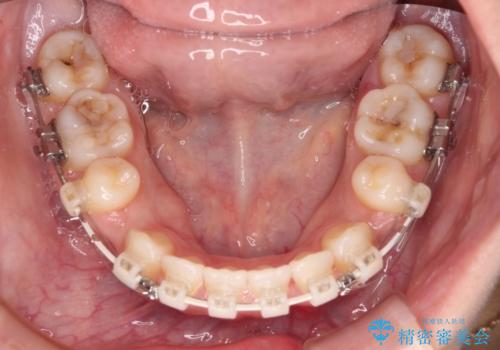

- 審美装置

- 2年6ヶ月

- 口元の突出感と上下前歯のズレを気にして来院された患者様です。

舌の突出癖により上下の前歯は非接触となっている状態でした。

舌のトレーニングを行わないと上下前歯の接触達成は困難であるため、トレーニングをしっかりと行っていただきながら、治療を進めて行くこととしました。

突出感改善のため、上下左右の第一小臼歯4本を抜歯し、ワイヤー装置にて矯正治療を行うこととしました。